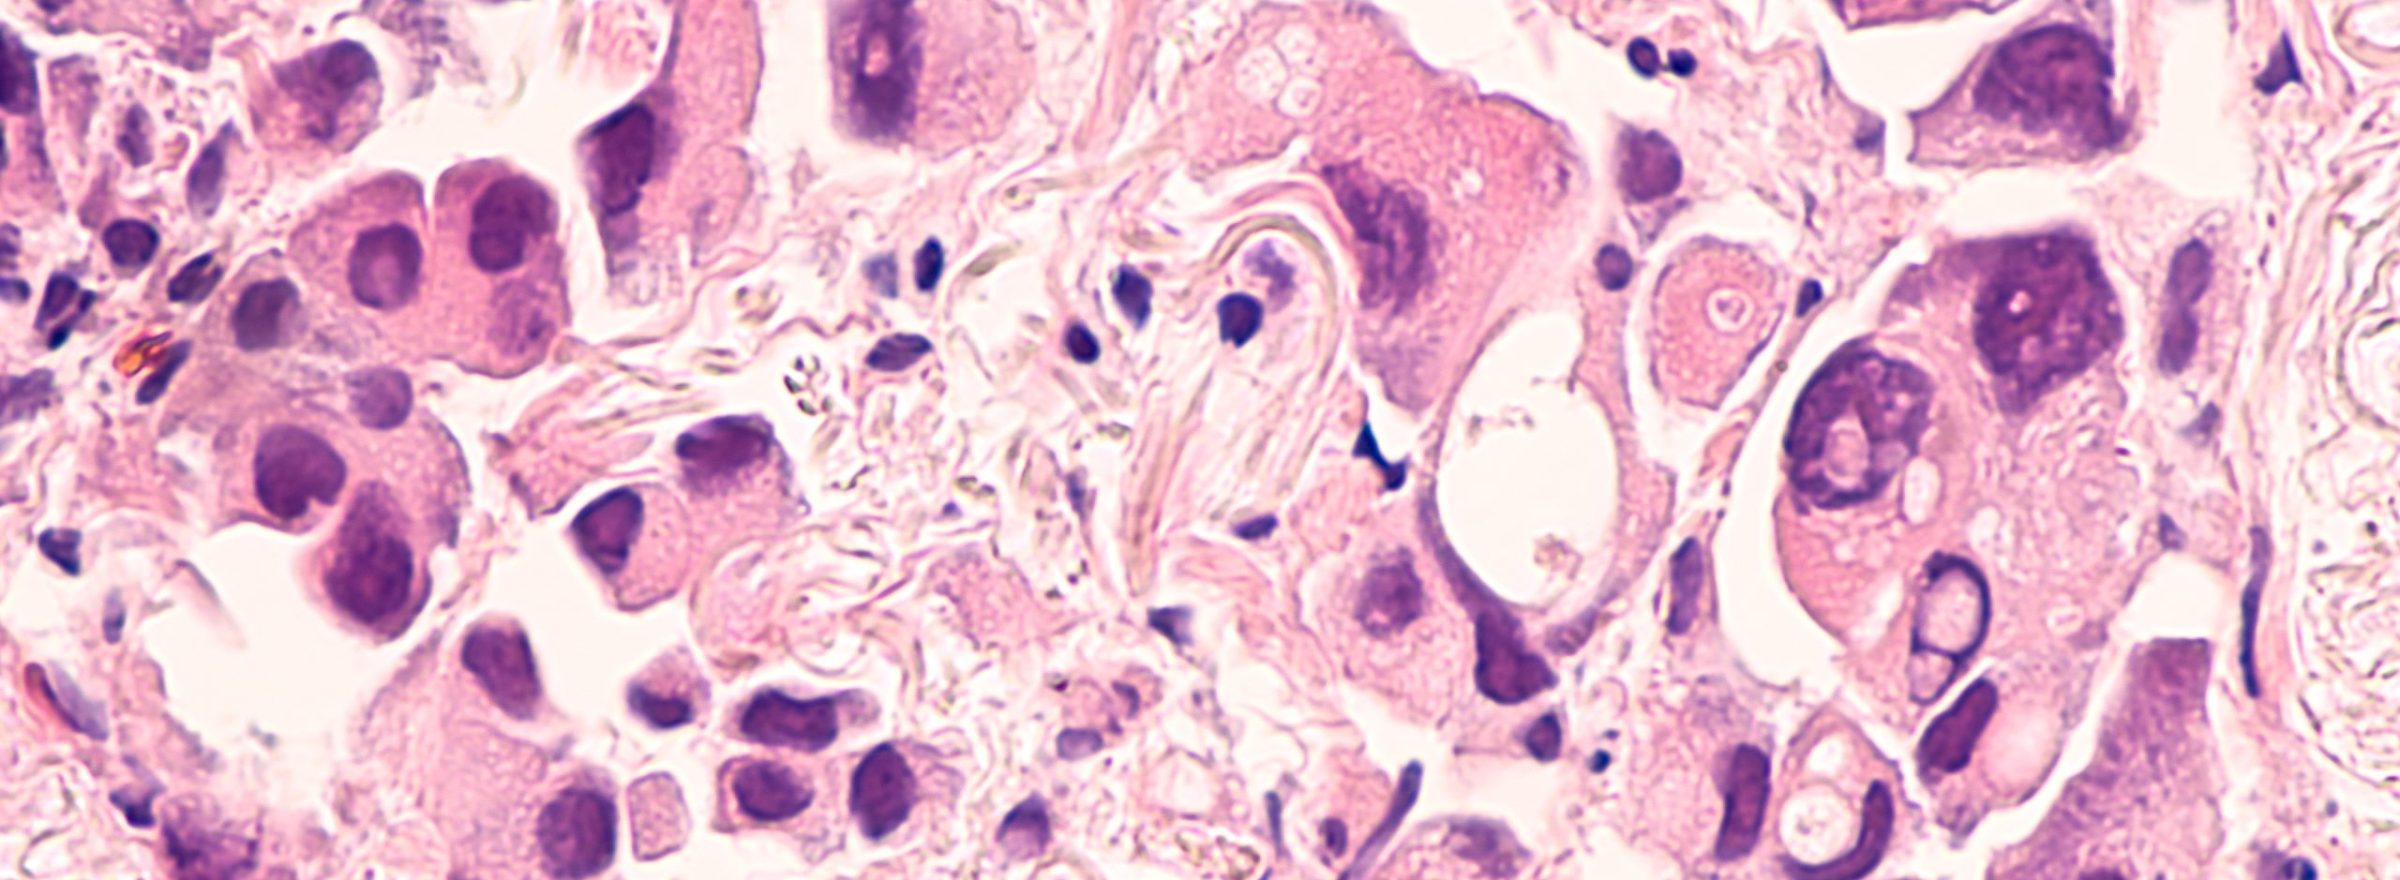

Mast cells are crucial players in the body’s defense mechanisms, orchestrating immune responses and contributing to the maintenance of homeostasis. However, when mast cells undergo excessive proliferation or activation, it can lead to chronic inflammatory disorders such as asthma. In a recent study by Choi et al, 2023, researchers have shed light on the role of a lung-specific protein called MCEMP1 in the regulation of mast cell proliferation and its implications in asthma development. Understanding the mechanisms behind mast cell expansion and its association with MCEMP1 opens new avenues for the development of targeted therapies for lung inflammatory diseases.

The study highlights that MCEMP1 acts as an adaptor for the KIT receptor, a crucial receptor involved in mast cell proliferation. MCEMP1 promotes the signaling pathway induced by stem cell factor (SCF), which binds to KIT, leading to mast cell proliferation. Through its cytoplasmic immunoreceptor tyrosine-based activation motif, MCEMP1 elicits intracellular signaling and forms a complex with KIT, enhancing its activation. The absence of MCEMP1 impairs SCF-induced mast cell proliferation both in vitro and in vivo, specifically in the lung. This suggests that MCEMP1 plays a vital role in facilitating SCF-mediated mast cell proliferation in the lung.

Asthma is characterized by chronic airway inflammation and impaired lung function. The study demonstrates that MCEMP1 deficiency in mice leads to reduced airway inflammation and lung impairment in chronic asthma mouse models. When subjected to OVA-induced chronic asthma, mice lacking MCEMP1 showed alleviated lung function impairment compared to control mice as measured by the flexiVent. Parameters such as lung stiffness, airway hyperreactivity, compliance of the respiratory system (Crs), elastance of the respiratory system (Ers), and tissue elastance (H) were improved in MCEMP1-deficient mice. These findings suggest that MCEMP1-mediated mast cell expansion contributes to the progression of airway inflammation and lung function impairment in asthma.